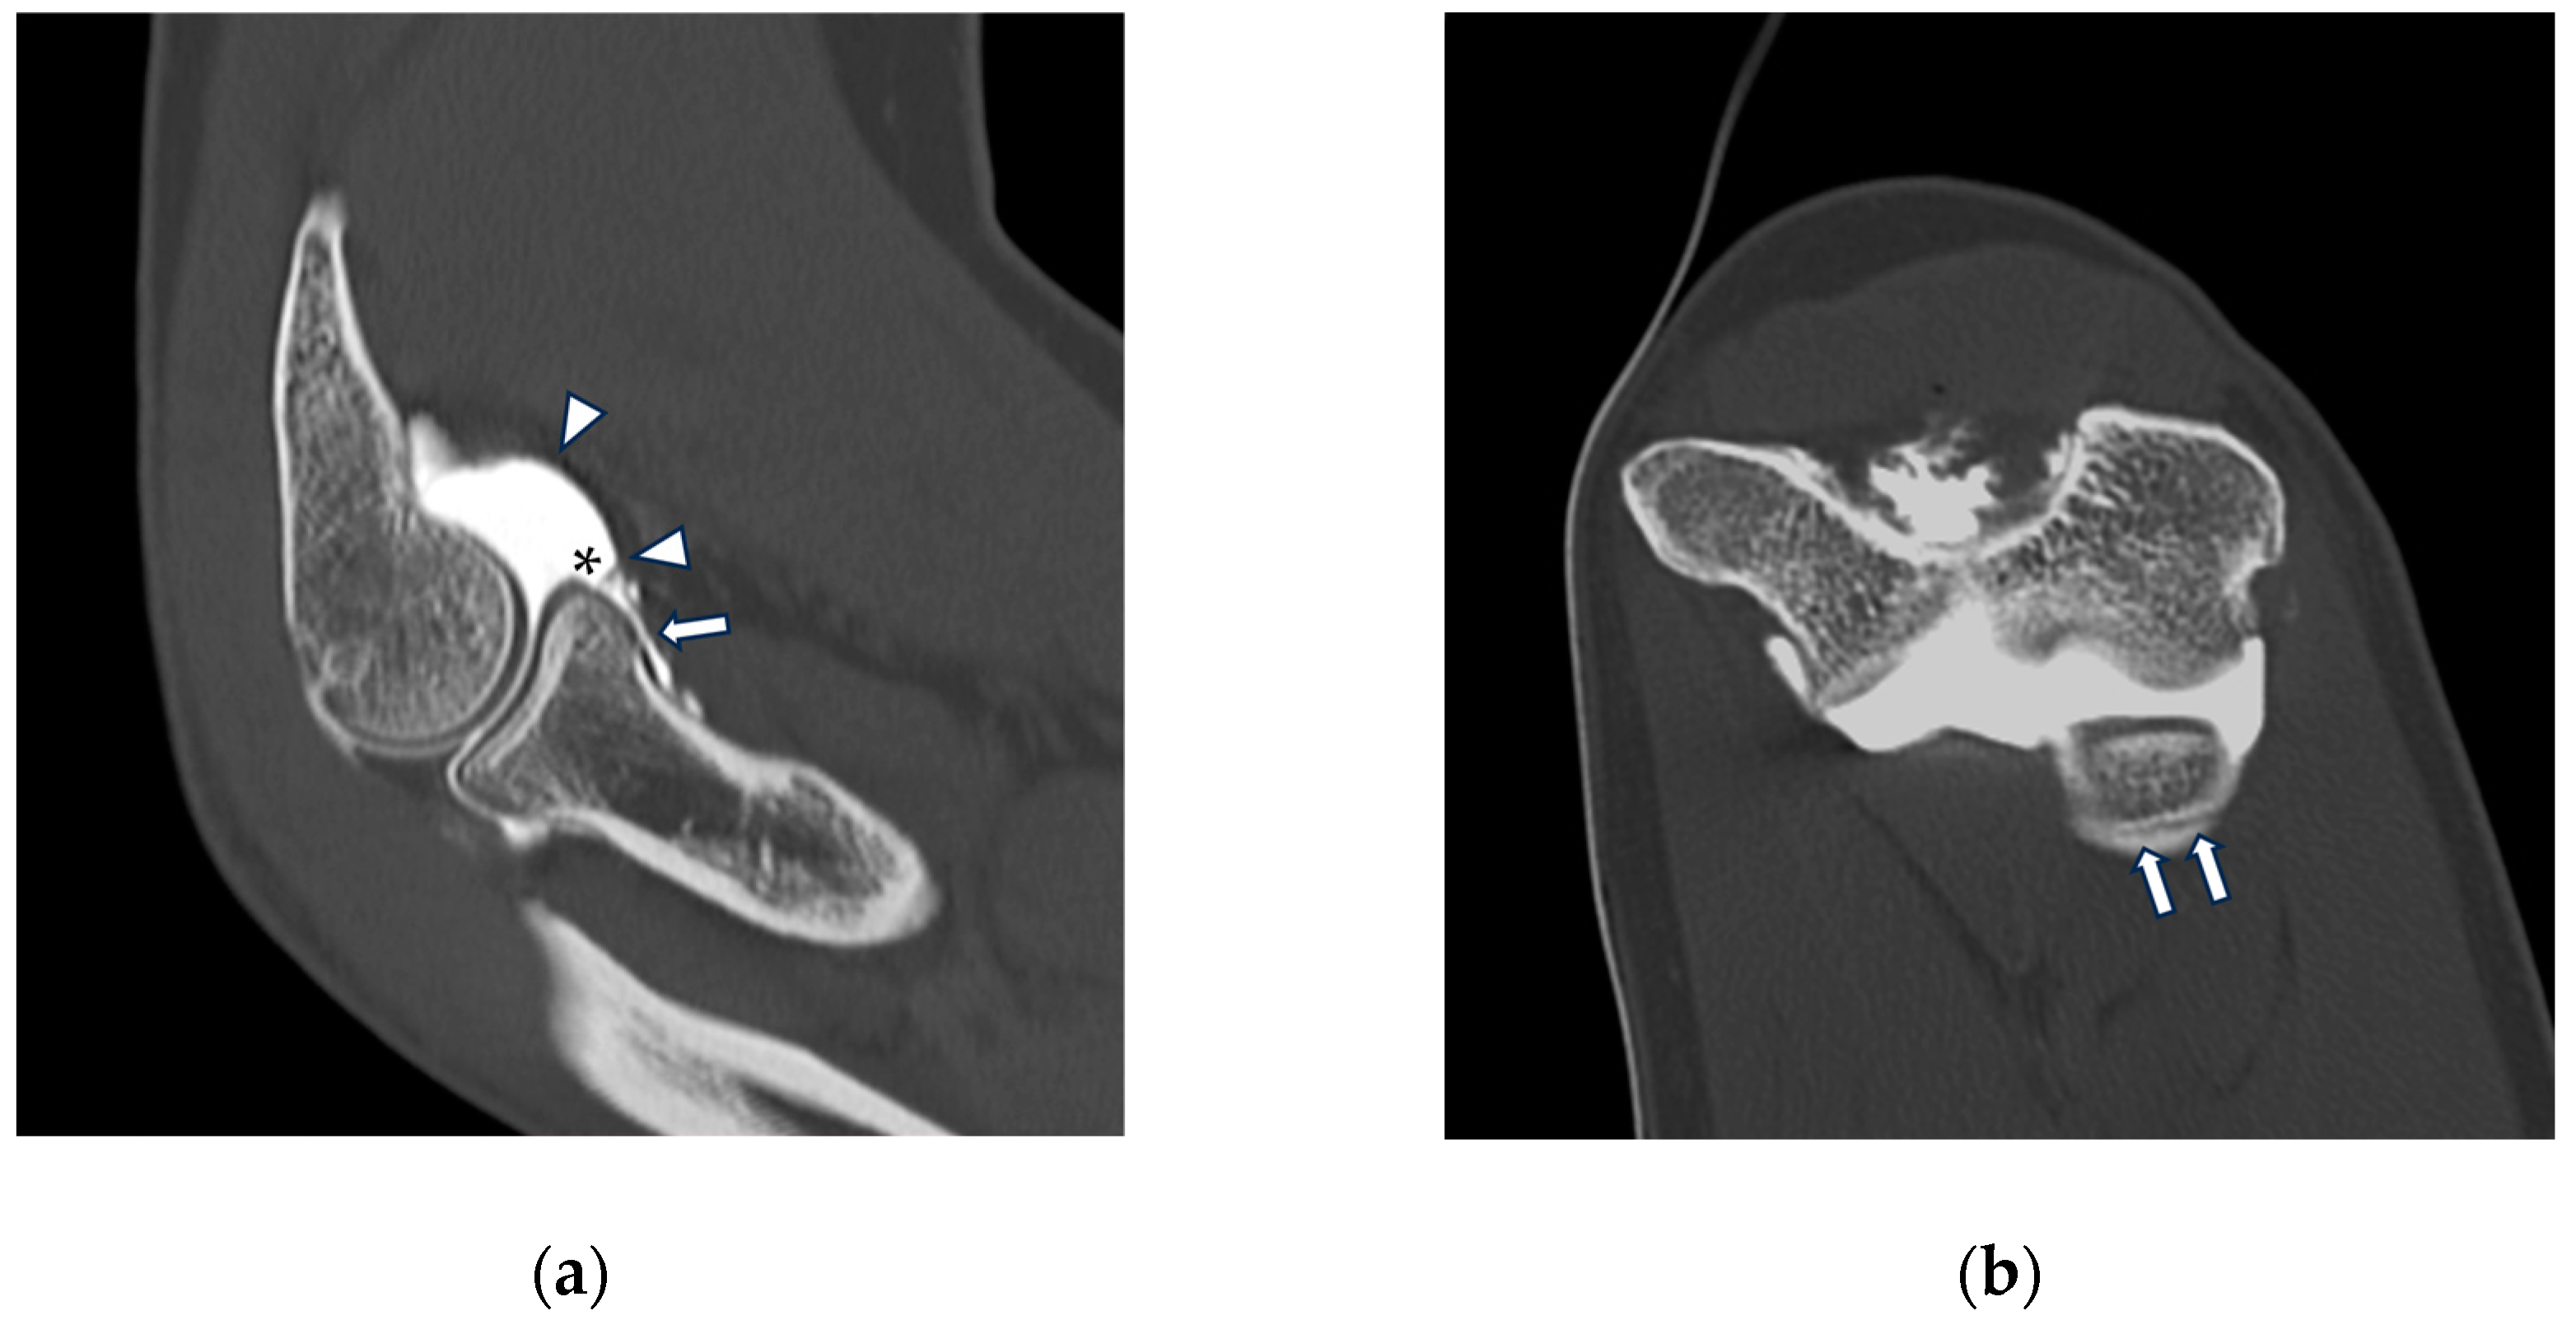

Figure 5.

CT arthrography of a patient with sequelae of traumatic elbow dislocation. (a,b) Coronal and axial images showing LCL laxity with subtle foci of contrast medium permeation due to ligament delamination (white arrowheads) and a loose body within a pathologically distended lateral recess (white arrow), as well as cartilage thinning and fraying of the lateral aspect of the capitulum humeri (yellow arrowhead). Post-traumatic deformity of the radial head can also be seen; (c) sagittal reformat shows a loose bony fragment posterior to the capitulum humeri (asterisk) and posterior synovial thickening (yellow arrow).